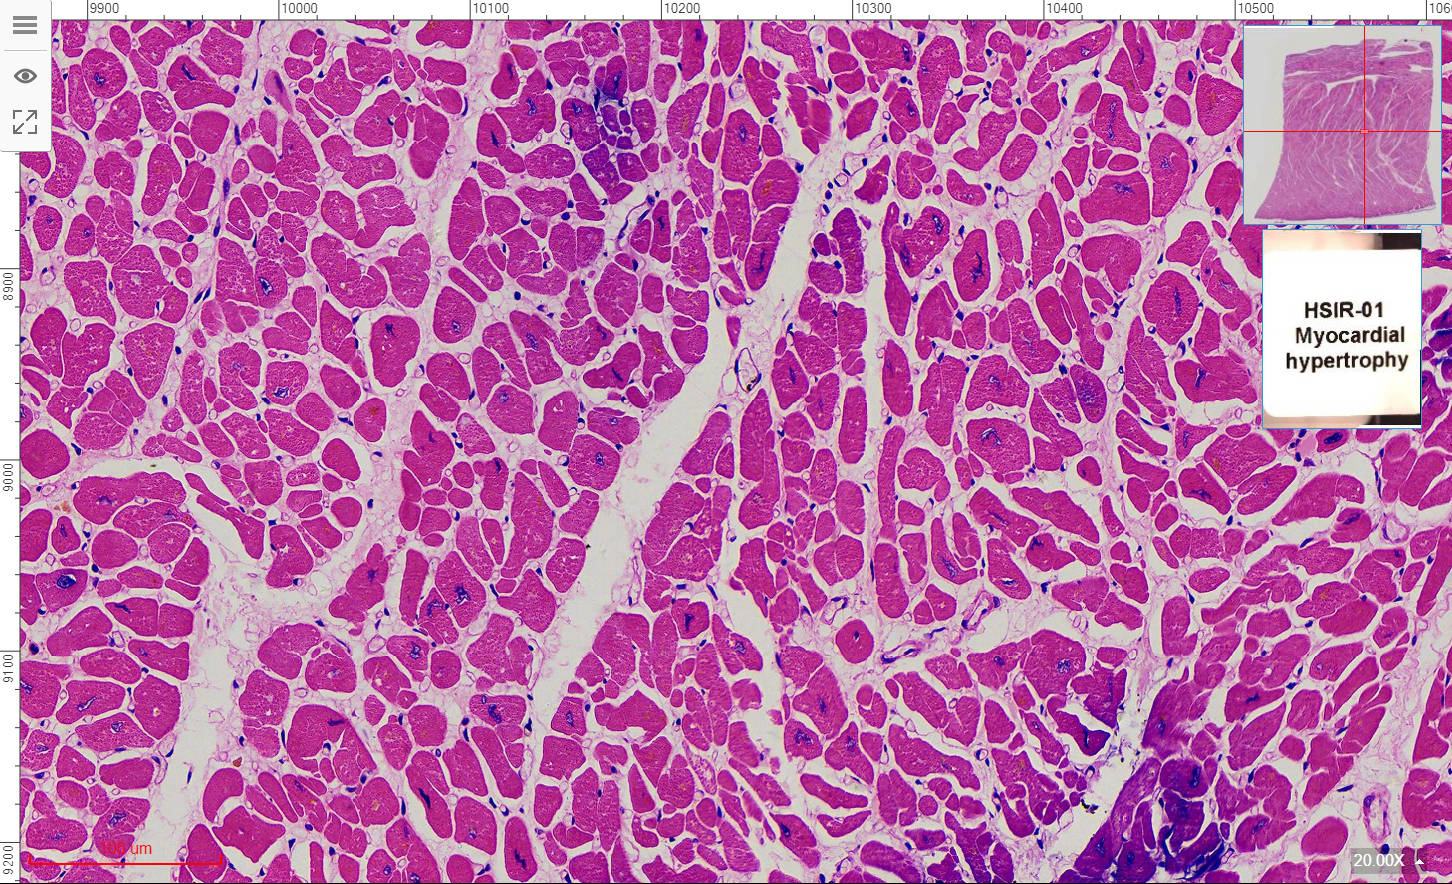

1, Injury and repair of cell and tissue

HSIR-01 Myocardial hypertrophy